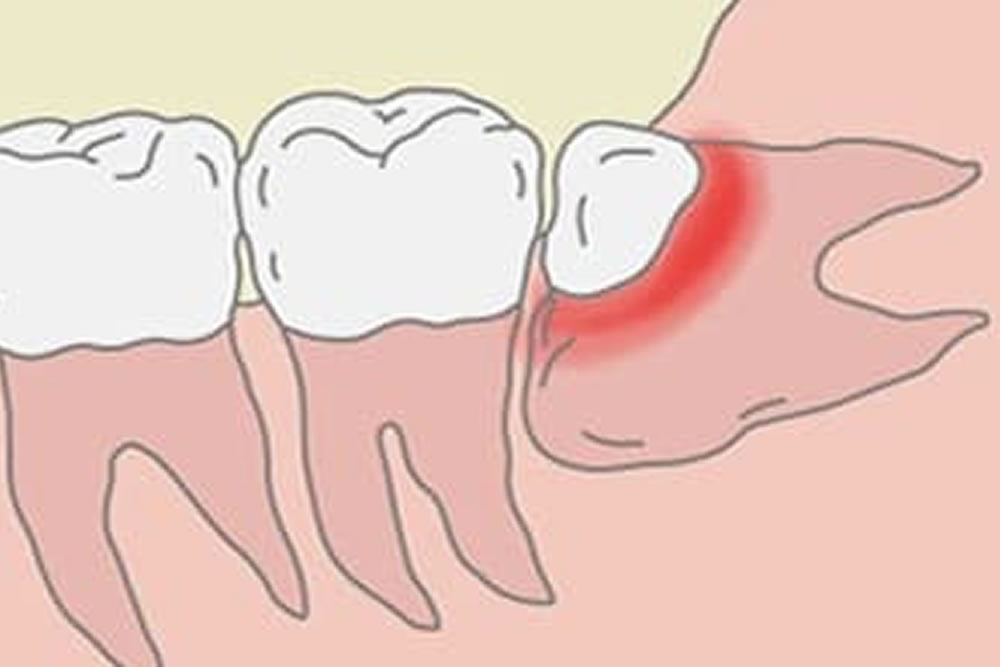

頻繁に智歯周囲炎を起こす

歯茎より上に一部分しか露出していない親知らずは、ケアが難しく、周囲に蓄積した汚れによって細菌が繁殖すると、炎症を起こしやすくなります。親知らずの周囲に生じる炎症は「智歯周囲炎」と呼ばれ、症状が悪化すると、痛みや腫れをはじめ、発熱や開口障害など様々な問題を起こす可能性があるため、抜歯をおすすめいたします。